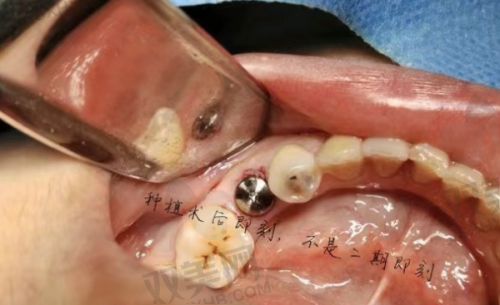

种植牙种的种植步骤通常较为复杂。首先是术前检查和评估,医生会对患者的口腔进行全方面检查,包括拍摄X光片、CT等,了解牙槽骨的情况、牙齿缺失部位等,以确定患者是否适合种植牙种。接着进行种植体植入手术,在局部麻醉下,将种植体植入牙槽骨内。这一过程需要医生有精细的操作,确保种植体的位置和角度合适。植入后需要等待一段时间让种植体与牙槽骨形成骨结合,这个时间一般为3 - 6个月。末尾进行牙冠安装,经过检查确认种植体与牙槽骨结合良好后,就可以安装合适的牙冠,完成整个种植牙种过程。